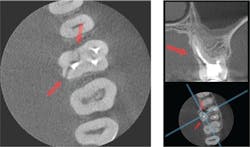

3-D technology allows for thorough treatment planning (figure 3). While I do not take a 3-D scan on every patient, 3-D images are captured when we feel the benefit outweighs the risk to the patient. Some examples of this are a failing root canal, a presurgical consultation to determine an odontogenic or nonodontogenic lesion, or if the source of the patient’s chief complaint is not obvious on the 2-D radiograph. Some other uses for CBCT are when I sense complicated anatomy, resorption, perforations, or instrument failures.

The 3-D imaging software also allows me to take measurements that I use in conjunction with my microscope to locate difficult anatomy in a conservative manner. Also, I can be more cautious when using a CBCT during treatment planning. The technology helps me confirm when not to treat certain “hopeless” teeth. Before implementing 3-D imaging, I would have had to open up the tooth or perform an irreversible procedure, only to discover that the tooth could not be saved.

It is interesting to note that when looking at a preoperative image with CBCT, 62% of clinicians change their treatment plans because they receive more information.1 Dental treatment changes when one has the full knowledge to create a more thorough treatment plan.